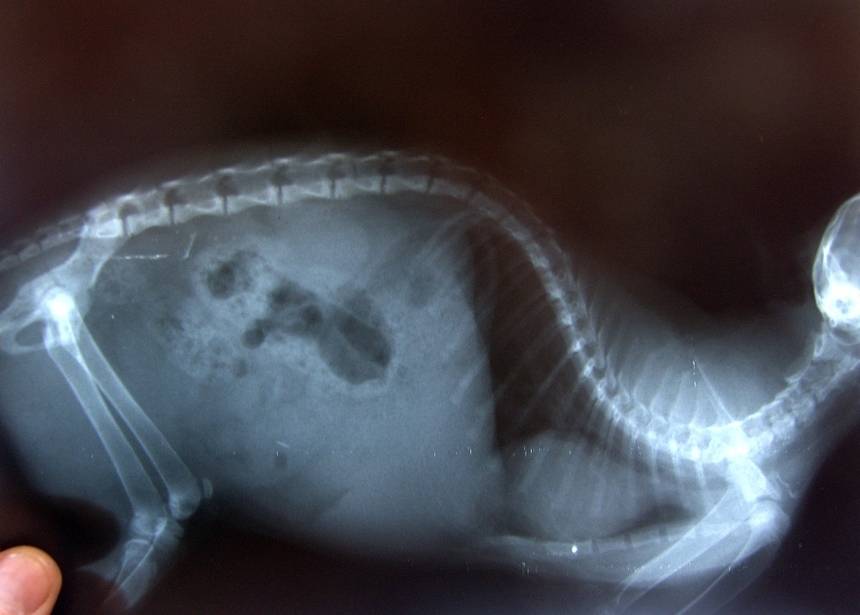

Нарушения в зоне энхондрального окостенения проявляются, в первую очередь, резким расширением зоны роста. В норме на рентгенограмме она имеет вид узкой ровной полоски, ширина которой в длинных трубчатых костях не более 1 мм. При рахите эта зона резко расширена, неровная.

Если заболевание быстро прогрессирует, доктор может направить ребенка на рентгенографию голеней и предплечий. По снимку можно определить снижение плотности костной ткани, увидеть нечеткие границы хрящей, расширение зон роста.

Рахит диагностирует семейный врач, педиатр, травматолог-ортопед. Врач осматривает ребенка и назначает рентгенологическое исследование костей скелета, прежде всего, рентгенографию трубчатых костей конечностей, черепа, рентгенографию позвоночника.

При рентгенографии выявляют бокаловидное расширение метафизов (участок кости между начальным и центральным участком), истончение и искривление центрального участка кости, остеопороз, пр.